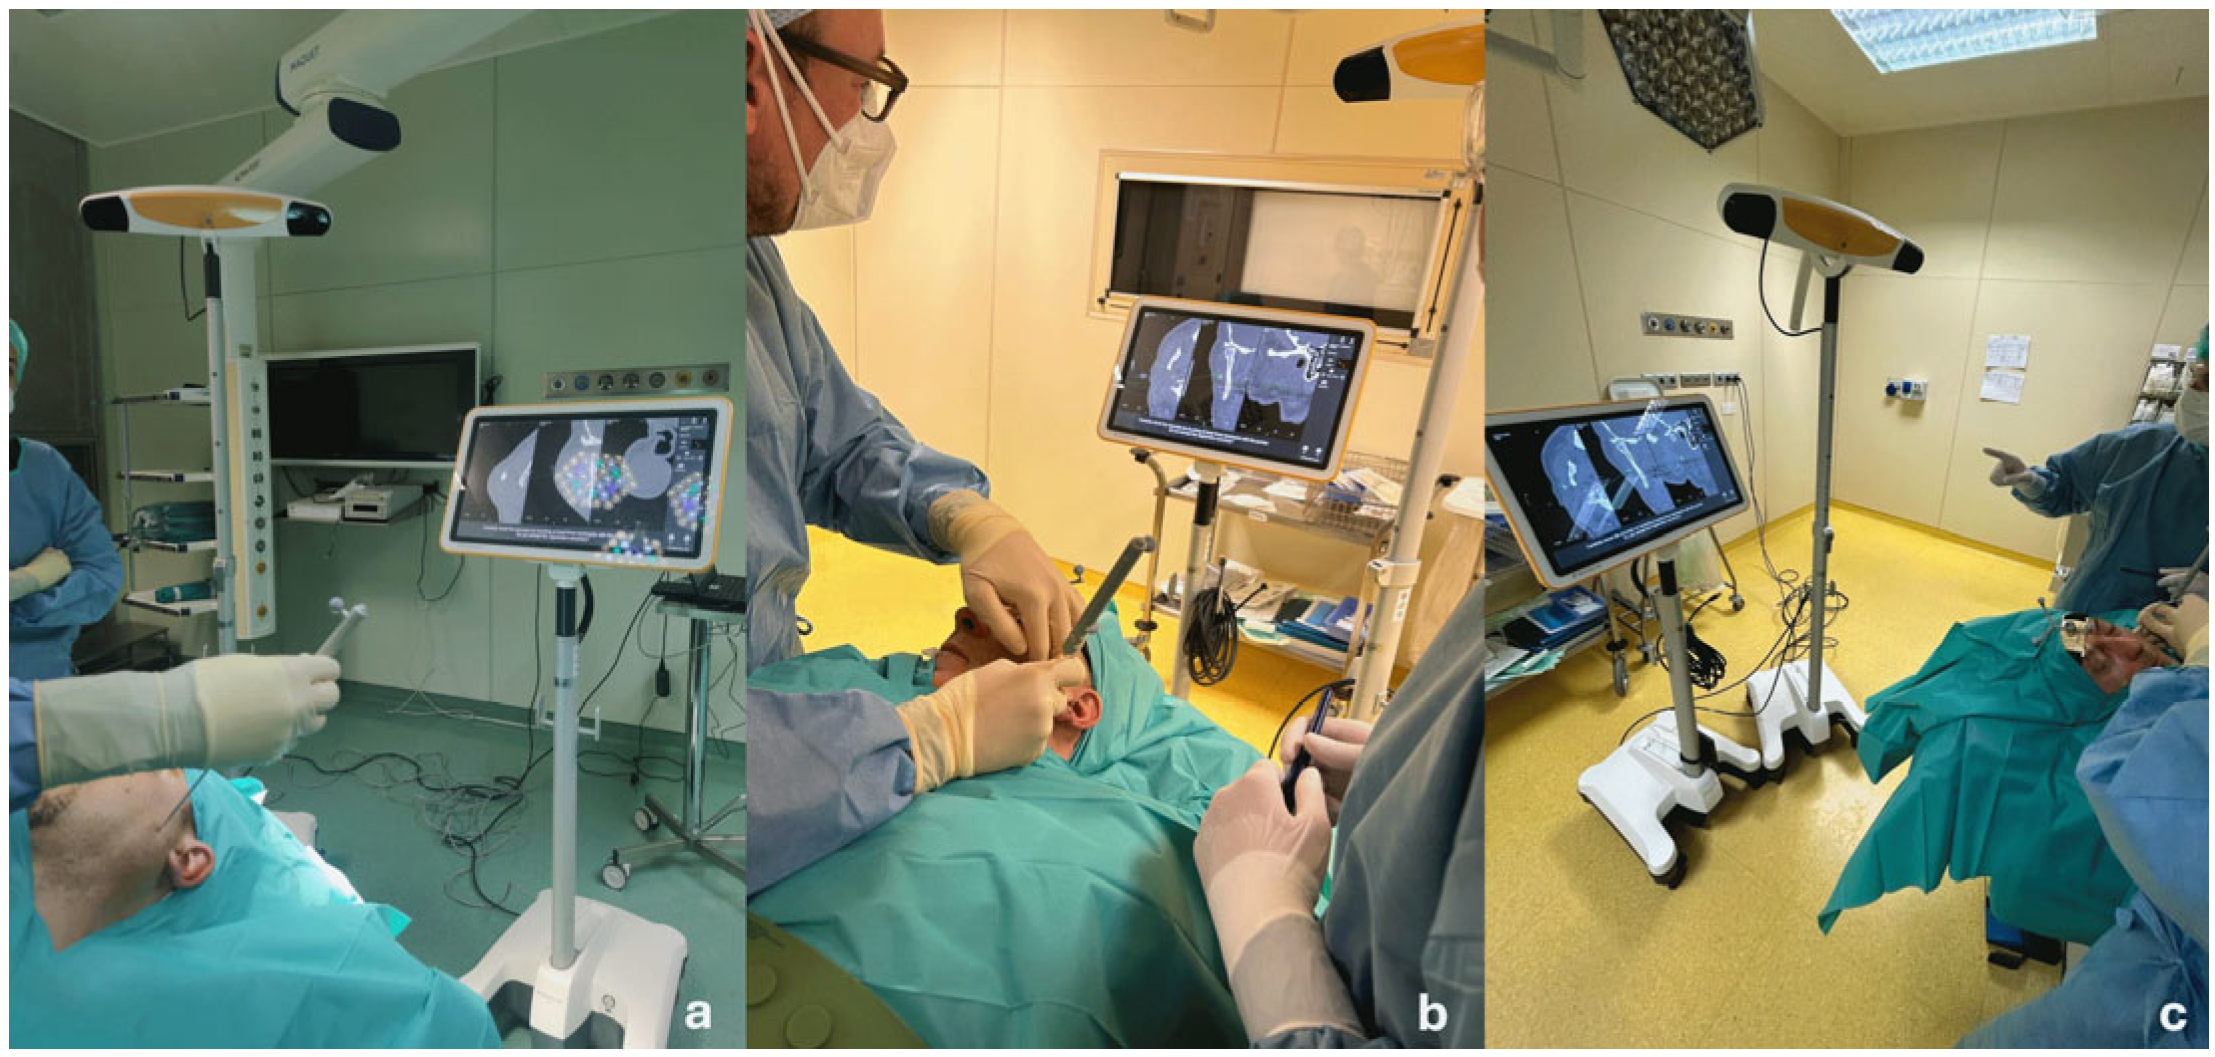

Before surgery, the patients’ digital imaging and communications in medicine data-set (DICOM) were imported on iPlan CMF 3.0 software (Brainlab, Munich, Germany) to set up the optical-based navigation system of the operating room (

Figure 1). A reference star array was attached to a headband on the head of the patients and a laser pointer was used to record landmark points on the face. During surgery, axial, coronal, and sagittal CT images, previously uploaded and reconstructed, were displayed on a kick display (Brainlab, Munich, Germany) to track the navigation pointer. The optical-based navigation was used to locate the stone (

Figure 2) and its position marked on the skin surface (

Figure 3). A preauricular skin incision was made, a skin flap was raised, and a blunt dissection, guided by the navigation system, allowed the exposure of the parotid gland and the subsequent exact localization of the stone as visualized on the display (

Figure 4). A neurostimulator (Neuro-Pulse

®, Bovie Medical Corporation, Clearwater, FL, USA) was used to check the functioning of the branches of the VII cranial nerve. The duct was then incised and opened under navigation guidance, and the stone was removed (